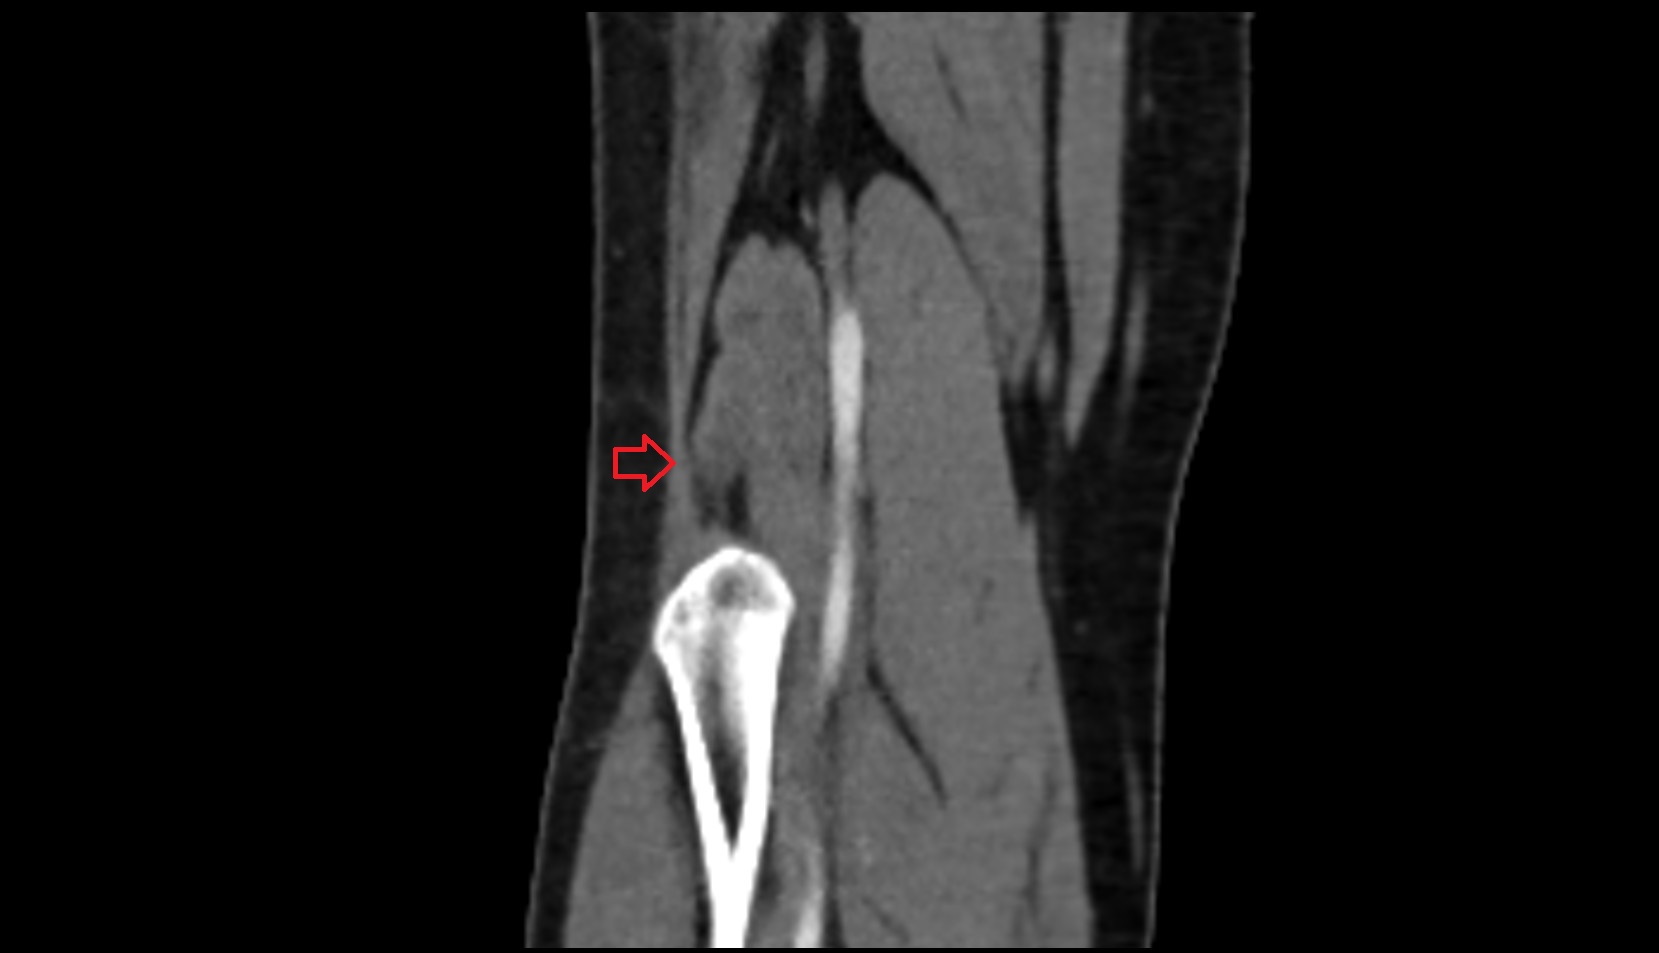

- Knee Joint